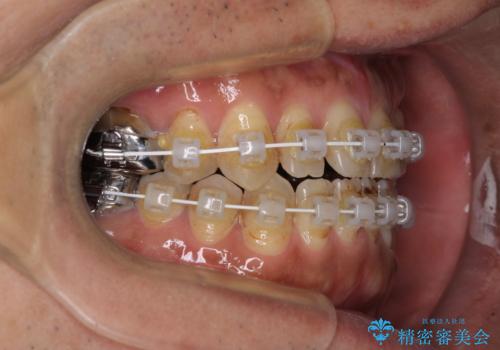

- 審美装置

- 1年11ヶ月

- 10-30回

前歯の反対咬合が改善する過程では、奥歯が咬みにくくなるため、食事では辛い思いをされていたようです。